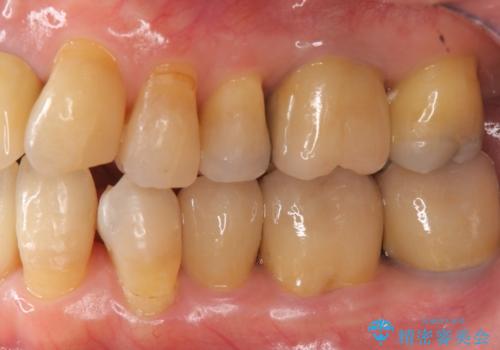

- 前歯の見た目・歯並び・銀歯の見た目の改善を求めて来院されました。

まずガタ付きの強い歯並びをマウスピース矯正インビザラインで整えたのち、セラミック治療による審美性の改善を計画します。

矯正治療が終わったのちに、精度の高いセラミックを装着することでより安定した噛み合わせとなり審美性も兼ね備えた口腔内状態で治療を終了し、今後のメンテナンスを行っていくことができます。